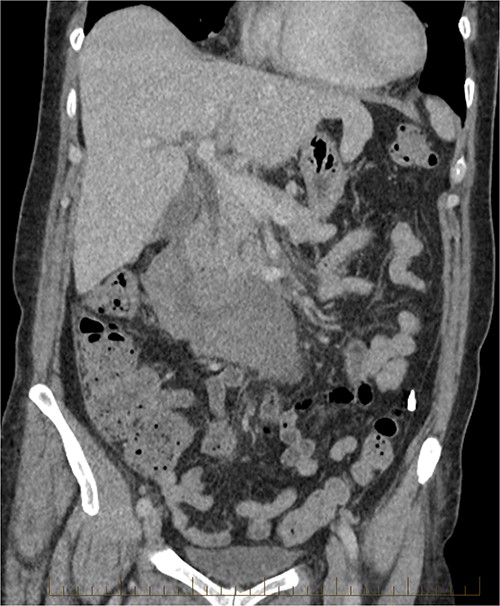

Continued observation, analgesia and fasting. On Day 2 post-admission, the patient had an urgent upper gastrointestinal endoscopy, which showed no abnormality. No ulcer, compression or inflammation was found. After the gastroscopy, the patient was started on a normal diet, which she tolerated well, and her pain had also improved. A progress CT was performed on Day 5, which showed a mild increase of the periduodenal collection with mass effect on the duodenum and evidence of mild biliary tree dilatation with the common bile duct measuring 11 mm. There was no sign of gastric outlet obstruction (Figs 7 and 8).

CT abdomen, coronal view. Slight interval decrease in size of previously identified periduodenal hematoma.